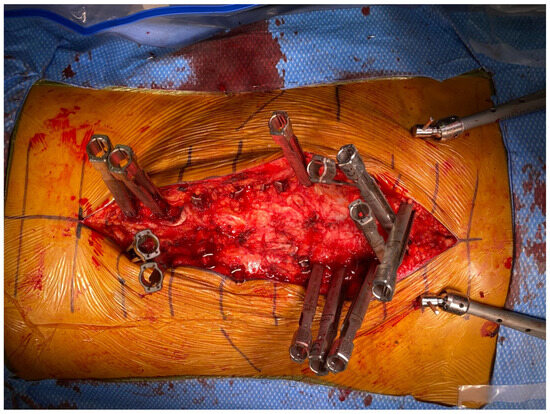

Figure 6. Intraoperative view showing a single skin incision with transfascial placement of all screws. Note extension towers were left off the L1-4 pedicle screws to facilitate visualization for subsequent mini-open posterior column osteotomies.

Stage 2 of the procedure is next carried out on the second operative day with the patient in the prone position. To minimize the introduction of movement error that could affect robotic accuracy, we add circumferential tape during positioning at the best pad below the axilla and at the distal buttocks. Anesthesia also administers muscle relaxant after monitoring baselines to limit delayed sag or patient movement during instrumentation placement. The robotics system is registered to the patient and screws are placed transfascially through a single midline skin incision or percutaneously through multiple incisions if the patient has a high BMI (Figure 6). All techniques are performed using what we term “light-touch surgery”, whereby all instruments pass down perfectly and smoothly coaxial to the robotic arm’s end effector to minimize its deflection; any sticking is treated with irrigation and xeroform. Screws are placed in a sequence that is proximal (UIV) to distal (S1), and then all S2-alar-iliac (S2AI) or traditional iliac screws are placed last. This is to ensure maximum accuracy with the screws furthest away from the system most vulnerable to movement error, and because the placement of iliac screws generates an incredible amount of torque that can introduce error into the system. If there is any concern of error, robot and navigation checks are performed or the patient is re-registered with updated C-arm X-rays out of an abundance of caution.

An intraoperative CT scan with a navigation frame attached to the patient is then obtained as a confirmation scan and to allow for navigated repositioning of any screws that are needed. A navigated burr is then used through the existing transfascial or percutaneous incisions to decorticate and drill out all facet joint levels that do not have anterior interbody fusions. These decorticated pockets are then packed with the bone graft of choice for the surgery. If needed, a mini-open exposure is performed for posterior column osteotomies (PCOs) to allow for further lordosis or scoliosis curve correction. Rods are then passed using a minimally invasive technique with rod passage inserters. While this historically has carried the possibility of great difficulty, the enabling technologies of planar screw planning has allowed this to proceed in very routine fashion. Satellite rods are first secured and locked into position so that their minimally invasive towers can be removed from the working airspace over the wound and any distractive techniques are completed if they are functional kickstand rods [16]. Placement of both main rods then follows. Acceptable alignment is then confirmed using a long film or a series of stitched X-rays (Figure 7). Closure proceeds in the usual fashion after all set screws are secured and towers removed.